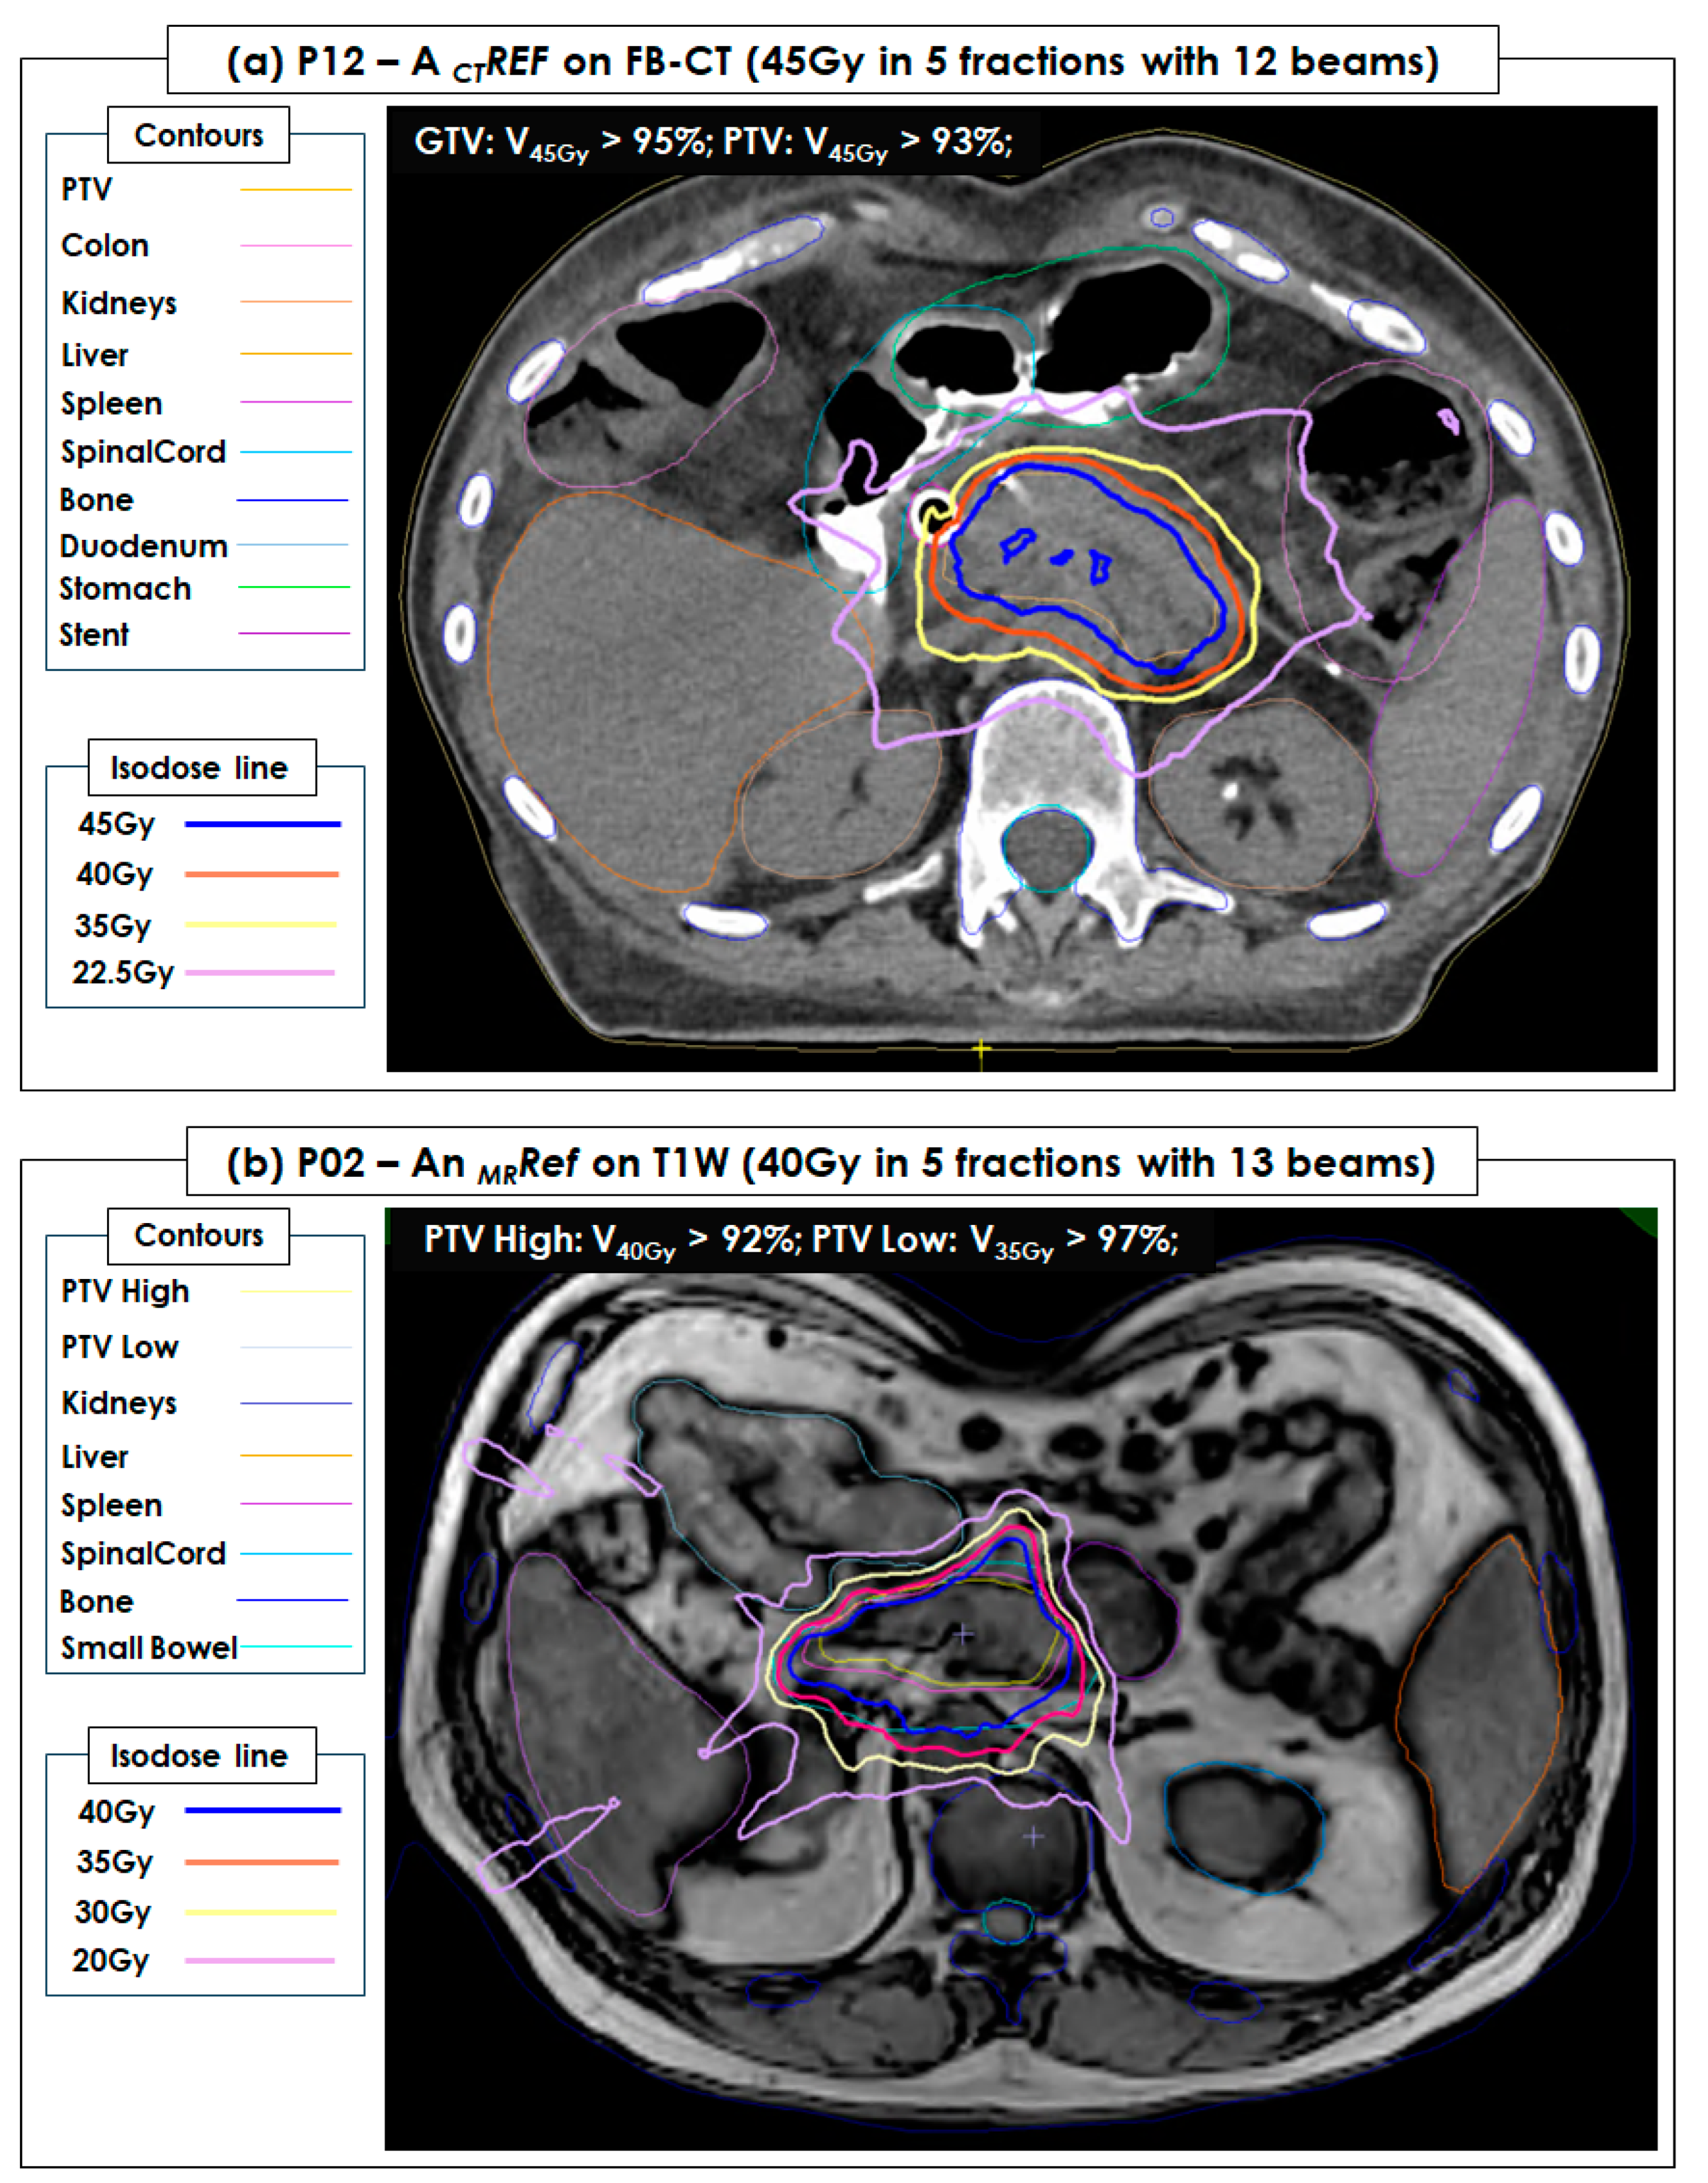

| P02 | Pancreatic head | 65 | M | 40 Gy in 5 fractions | 13 | ATP (n = 0), ATS (n = 5) |

| P12 | Pancreas head/body | 83 | M | 35 Gy in 5 fractions | 11 | ATP (n = 0), ATS (n = 5) |